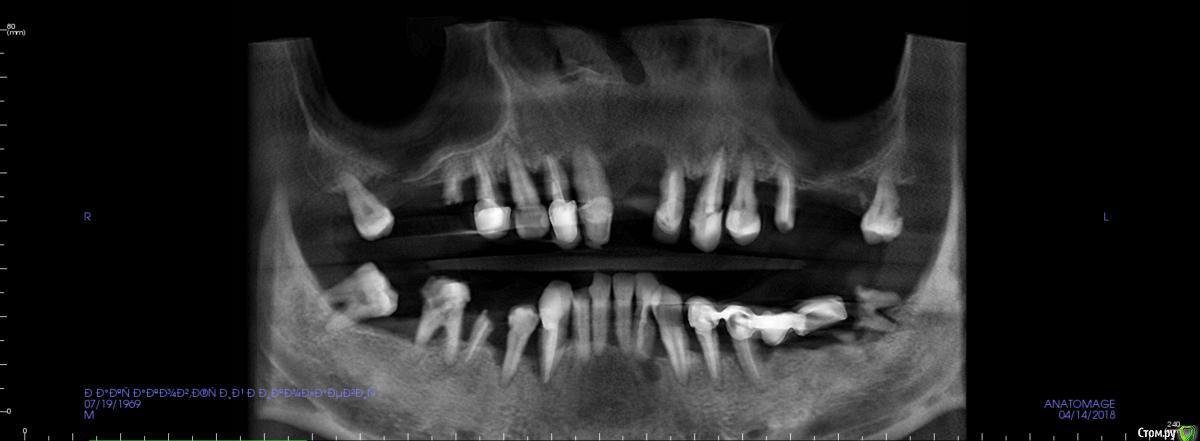

JurJul Опубликовано 17 апреля, 2018 Поделиться Опубликовано 17 апреля, 2018 Не знаю, возможно мой случай в раздел протезирования и не подходит, возможно нужна хирургия и имплантация. История. Живу в Белоруссии. В 2000 году сделал всё, что нужно было: мосты, коронки, виниры на передние зубы. На то время по высокому уровню стоматологии. Где-то через 2 года обнаружили онкологию (семенома) на 1 стадии. Операция, химия, лучевая. Препараты на химиотерапии этопозид, цисплатин. Всё благополучно прошло. Потом где-то через 2-3 года мосты и коронки стали беспокоить и постепенно они снялись. В начале 10-х годов был на нескольких консультациях - сказали, что у меня 2 варианта: ждать пока само всё выпадет и потом ставить всё полностью съемное "под Карегу" и второй вариант - удалять всё раньше и опять же ставить полностью под Карегу. Я как-то не могу с этим смириться, всё же думаю, что возможны варианты ещё, тем более, что научно-технический как и медицина со своими технологиями двигаются семимильными шагами. Про импланты мне говорили, что в моём случае ничего не будет стоять, т.к. была в прошлом химия и лучевая и у меня всё подвижно, что собственно подтверждается состоянием зубов и корней, которые норовят выходить сами. Были частые воспаления дёсен и признаки пародонтоза. В последние месяцы стали шататься передние верхние, прямо похоже как у детей, когда зубы меняются... И вот совсем недавно выпал (помог ему немного) верхний 1-ца. Бисфосфонаты не принимал. Зубы после онко удалял. Лунки заживали нормально.В субботу 14.04 был на консультации у имплантолога. Ведущий специалист в этой области в РБ... во всяком случае так его позиционирует Гугл )) Так вот мне сразу был предложен самый оптимальный в моём случае вариант - всё на 6 на обе челюсти и всё сразу и быстро. Удаляем всё и сразу и тут же вкручиваем импланты (Израиль или Нобель). Через 5-7 дней ставим временный несъемный протез и через полгода вуаля постоянный несъемный (либо керамику либо цирконий по желанию). Типа это в моём случае самое оптимальное и не очень тяжёлое в физическом и психологическом плане (сразу с зубами, не нужно съёмный протез полгода носить или без зубов долго ходить )... Я, честно говоря, не готов на такой вариант... Я понимаю, что возможно хороших зубов, которые смогут служить опорой под мост/ы, может и нет. И, возможно, и нужно будет всё удалить... Но я думаю, может и ошибаюсь, что есть и др. методы имплантации, если это неизбежно. Как мне сказали на консультации, что предложенный вариант единственный для верхней челюсти, варианты могут быть по низу, но по верху - без вариантов...Озвучена по стоимости работа "под ключ" : с израильскими имплантами 12 тыс. дол. , с американскими 20 тыс. дол. Дело даже не в стоимости. Просто мне не хотелось бы стать одним из авторов стом. форумов с мольбой о помощи в исправлении чьей-то работы с имеющимися проблемами. Больше всего на свете я не хочу проблем и переделок. Я понимаю, что на 100% нельзя быть уверенным в результате, но минимизировать риски, выбрав самый лучший или оптимальный вариант, можно. Вот поэтому я решил обратиться сюда за консультацией. Ссылка на 3D томографию: https://drive.google.com/open?id=1puDkkPZG_C-UQCklhUjX5sdAS_SOIooZВзываю к помощи товарищей врачей! Только на вас уповаю Ссылка на комментарий

St. Опубликовано 17 апреля, 2018 Поделиться Опубликовано 17 апреля, 2018 Обзорные срезы ( верх, низ, топография нижнечелюстного нерва), дефект в обл 21 Ссылка на комментарий